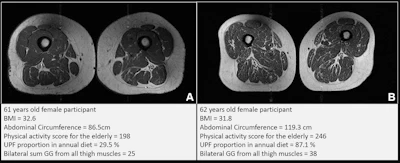

Representative axial T1-weighted spin-echo thigh MRI scans in (A) a 61-year-old female participant and (B) a 62-year-old female participant. Both participants were of similar age and body mass index (BMI, calculated as weight in kilograms divided by height in meters squared). Both had Physical Activity Scale for the Elderly scores above the mean score in the study. According to the World Health Organization definition, the participant in B qualified as having abdominal obesity (abdominal circumference ≥ 88 cm). Abdominal circumference is a measure of central obesity that captures fat distribution and serves as an indicator of cardiometabolic health. Compared with the participant in A, the participant in B had a higher proportion of ultra-processed food (UPF) in their diet (87.1% vs 29.5%) and exhibited fattier thigh muscles bilaterally, with Goutallier grade (GG) for all thigh muscles summing to 25 for the participant in A and 38 for the participant in B.RSNA